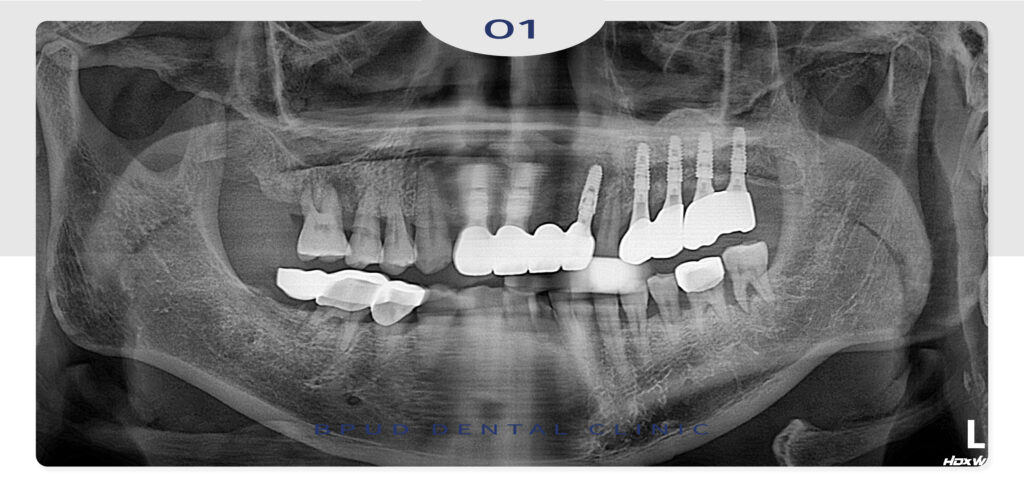

오늘은 골흡수가 심하게 진행된 부위

상악동 거상술을 동반한 임플란트 식립과

앞니 파절로 인해 상실된 부위를

임플란트로 회복하신 환자분을

소개해 드리려고 합니다.

왼쪽 위 작은 어금니부터 큰 어금니까지

모두 충치도 심하게 진행되었고 치주염도

심한 상태라 모두 발치를 하고 임플란트 식립이

필요한 상황임을 설명드렸습니다.

하지만 잇몸뼈가 이미 많이 녹아

많은 양의 뼈이식이 필요하여 상악동 거상술이

함께 필요한 상황이어서 동시에 계획을 수립하여

당일 모두 발치 즉시 상악동 거상술 및 임플란트

식립을 진행하였습니다.